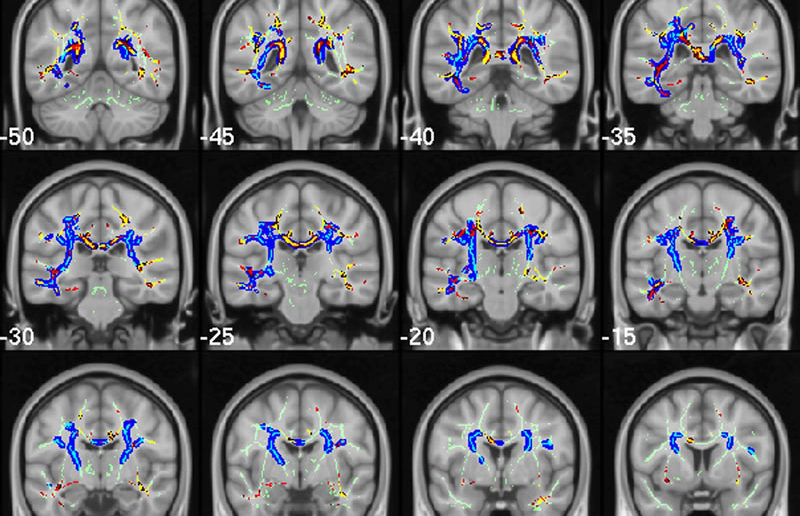

Brain scan. Image from Acosta-Cabronero et al.

This study is just one example of the vast Alzhimeimer’s research currently underway. For example, this past Wednesday we published a brain imaging study investigating potential biomarkers for Alzheimer’s that could facilitate early diagnosis, from Julio Acosta-Cabronero of the University of Cambridge and colleagues, and in September, we published a paper describing genetic signatures in mitochondrial DNA associated with a reduced risk for the disease from a group led by John Kauwe of Brigham Young University.

Acosta-Cabronero J, Alley S, Williams GB, Pengas G, Nestor PJ (2012) Diffusion Tensor Metrics as Biomarkers in Alzheimer’s Disease. PLoS ONE 7(11): e49072. doi:10.1371/journal.pone.0049072